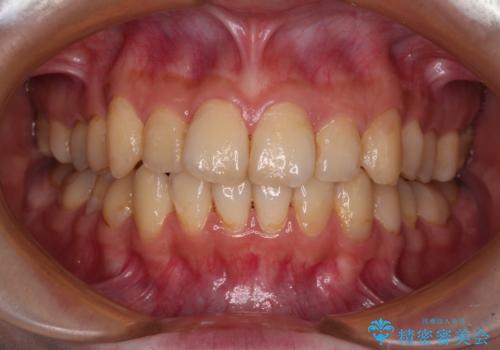

[ ディープバイト ] 深い噛み合わせの改善 マウスピース矯正

![[ ディープバイト ] 深い噛み合わせの改善 マウスピース矯正の症例 治療前](https://seimitsushinbi.jp/wp/wp-content/uploads/2022/03/dc9c092565b160bca6dd53d63f6aeffb-500x350.jpg?v=1646893459)

![[ ディープバイト ] 深い噛み合わせの改善 マウスピース矯正の症例 治療後](https://seimitsushinbi.jp/wp/wp-content/uploads/2022/03/5f1b12b750c3b8c04cdc49e53bc8f89d-500x350.jpg?v=1646893434)